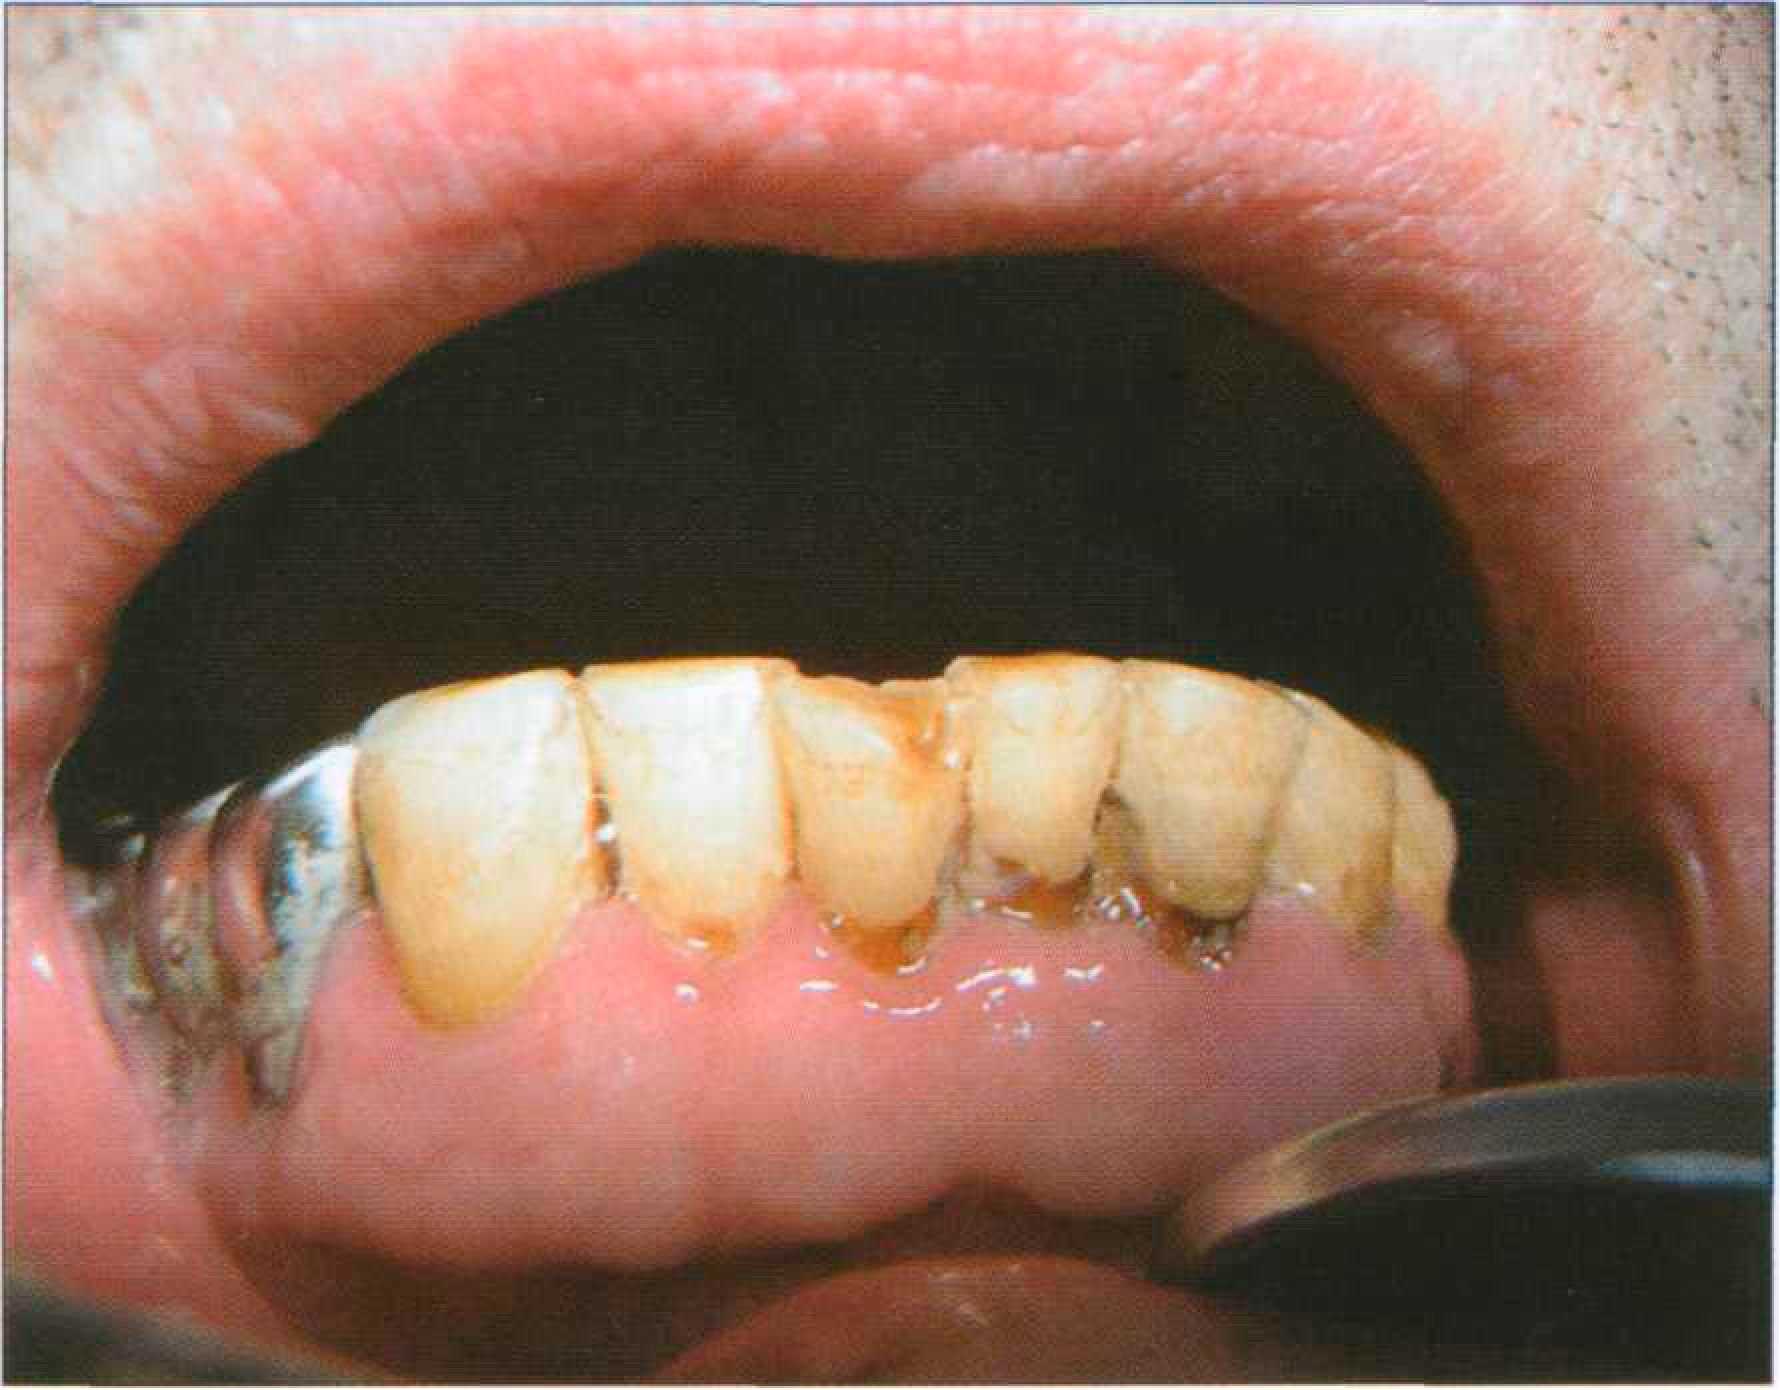

Благодаря высокой пористости участки деминерализации могут пигментироваться, приобретая желтоватую, бурую, коричневую окраску в зависимости от воздействующего красителя. Пары брома и йода окрашивают пришеечные области зубов в желтоватый цвет. Коричнево-черный налет на зубах появляется у лиц, занятых обработкой металлов (марганец, железо, никель). Хроническое отравление ртутью, сулемой, свинцом приводит к диффузному окрашиванию зубов различной интенсивности от серого до черного или от желтого до коричневого цвета. Особо следует остановиться на пигментации зубов у курильщиков (экзогенное, системное, поверхностное и глубокое окрашивание). Наиболее характерно образование темно-коричневого, почти черного налета вдоль шеек зубов, а также на тех поверхностях, которые не участвуют в жевании и плохо очищаются. Образованию «налета курильщиков» способствует плохая гигиена полости рта (рис. 173 а, б).

Рис. 173. Выраженная пигментация язычной поверхности резцов: налет "курильщика" — а; состояние после профессиональной гигиены — 6 Сходная окраска, которую можно отнести к воздействию пищевых пигментов, однако менее интенсивная и менее стойкая, чем у курильщиков, наблюдается у любителей крепкого чая и кофе. Содержание в питьевой воде железа может вызвать устойчивую синеватую окраску зубов. Выраженная пигментация органических покровов зуба может появляться в результате воздействия хлоргексидина, который назначают для полосканий (рис. 174).